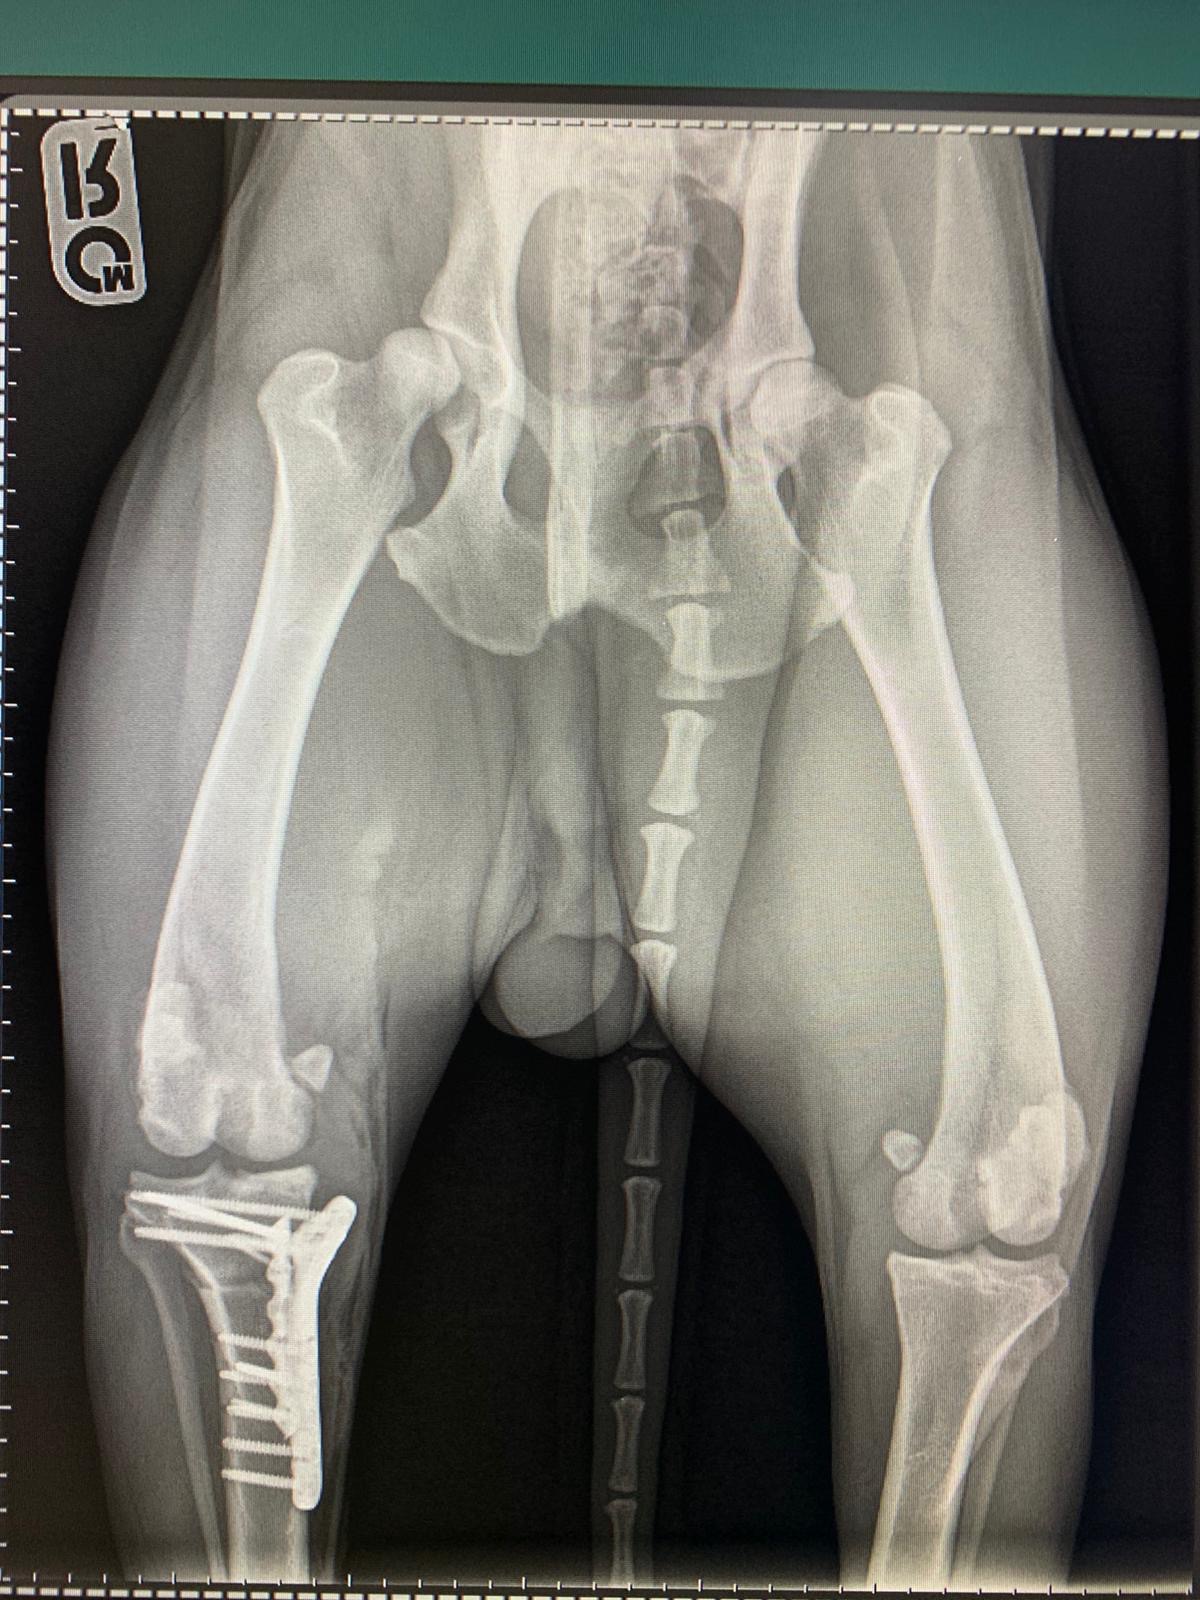

Hirurško liječenje rupture prednjeg križnog ligamenta koljena - TPLO

Za razliku od tradicionalnih metoda koje pokušavaju zamijeniti ili rekonstruisati ligament, TPLO mijenja biomehaniku koljena. Tokom zahvata, hirurg reže tibijalnu ploču (gornji dio goljenične kosti) i rotira je pod precizno izračunatim uglom kako bi se smanjio nagib zgloba. Time se eliminira klizanje femura po tibijalnoj ploči, koje nastaje zbog puknuća ligamenta, i stabilizira koljeno bez potrebe za ligamentom.